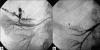

We report a case of Wunderlich's syndrome in an obese woman associated with massive retroperitoneal hemorrhage. Stable hemodynamic patient condition was obtained by selective arterial embolization. Since the first embolization of a renal angiomyolipoma in 1976 by Moorhead et al., highly selective renal arterial embolization of angiomyolipoma with rupture has become a procedure that offers greater efficacy, particularly in life-threatening cases.